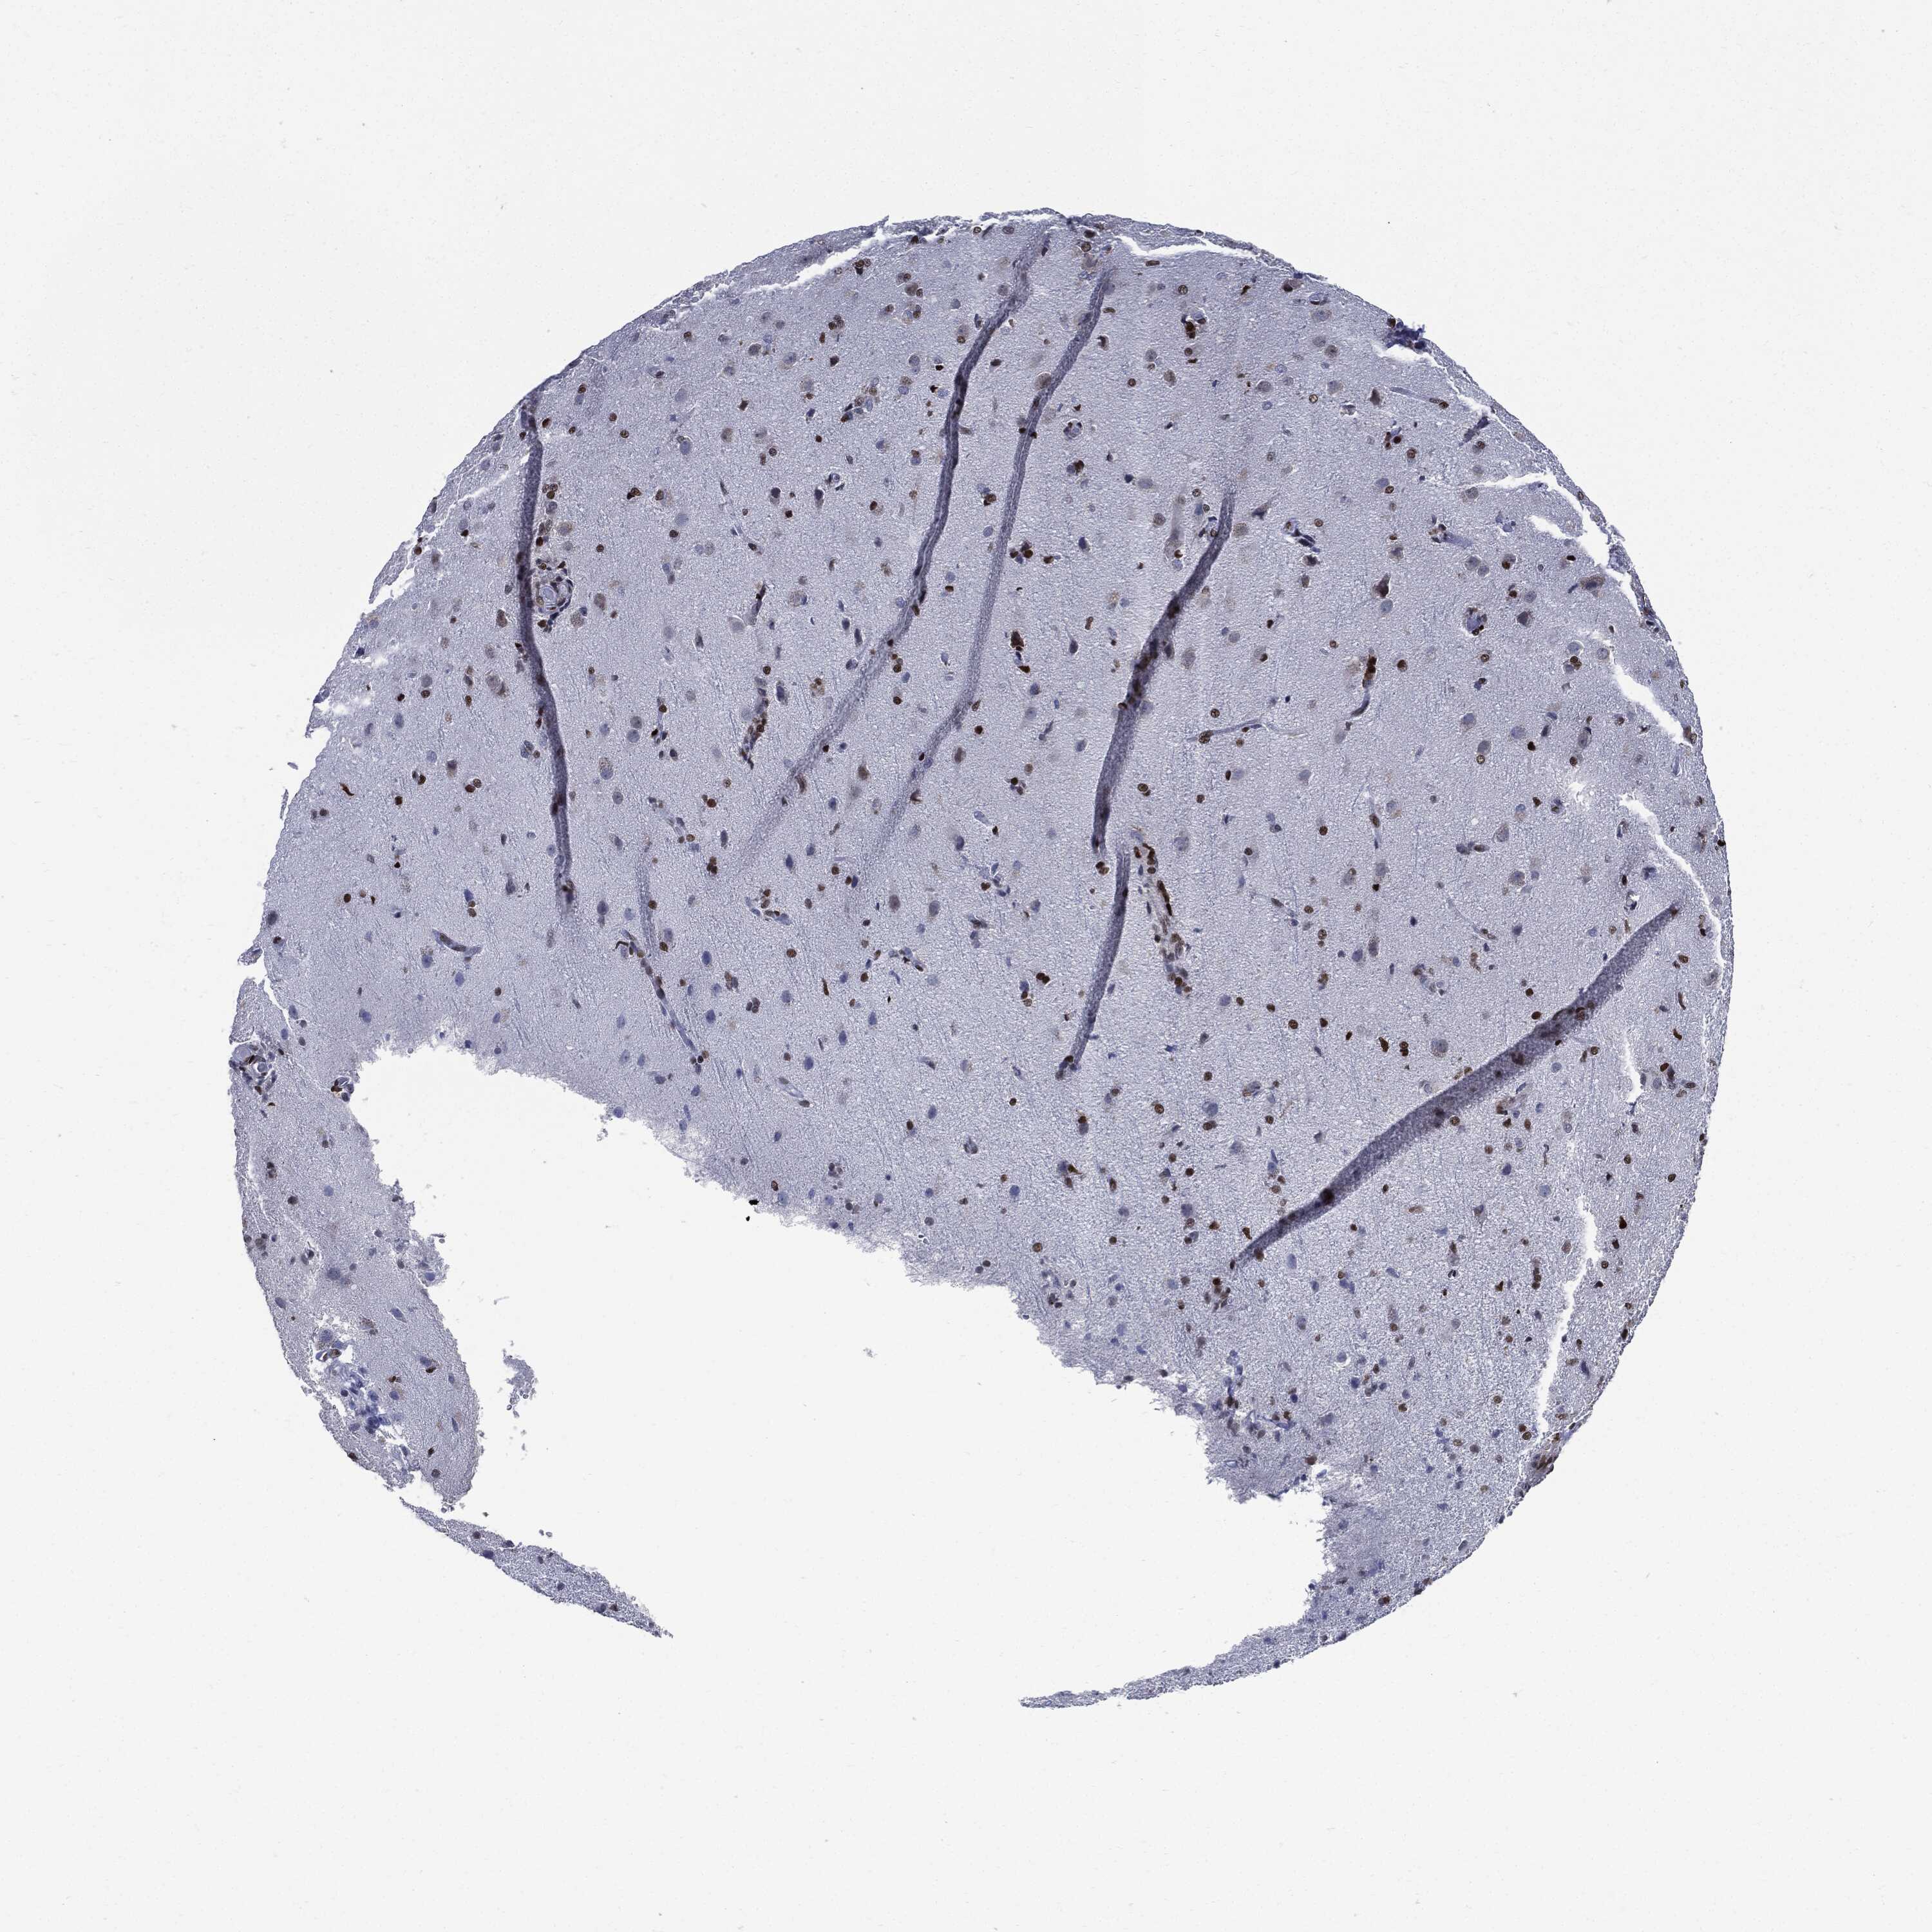

GLIOMA - Protein expressioni

A mouse-over function shows sample information and annotation data. Click on an image to view it in a full screen mode. Samples can be filtered based on level of antibody staining by selecting one or several of the following categories: high, medium, low and not detected. The assay and annotation is described here.

Note that samples used for immunohistochemistry by the Human Protein Atlas do not correspond to samples in the TCGA dataset.

Antibody stainingi

Antibody staining in the annotated cell types in the current human tissue is reported as not detected, low, medium, or high, based on conventional immunohistochemistry profiling in selected tissues. This score is based on the combination of the staining intensity and fraction of stained cells.

Each image is clickable and will lead to virtual microscopy that enables deeper exploration of all samples and also displays staining intensity scores, fraction scores and subcellular localization as well as patient and tissue information for each sample.

Glioma, malignant, High grade

Glioma, malignant, Low grade

Glioblastoma, NOS